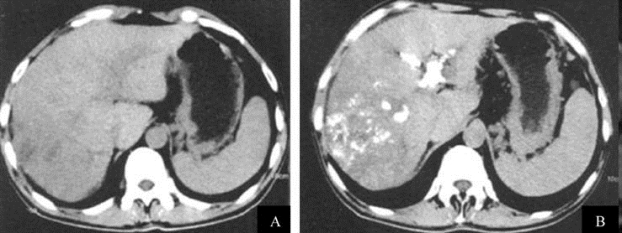

射频消融

(图21-26,图21-27);③生物免疫制剂或基因制剂等。